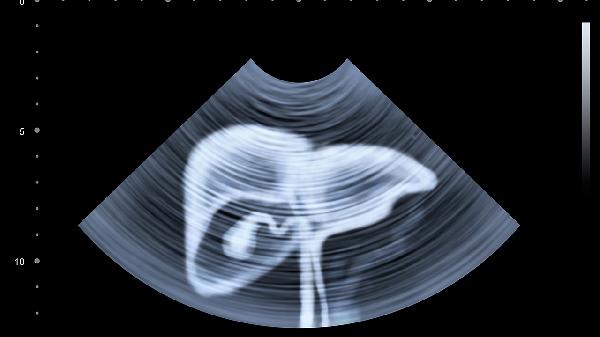

建议出现持续性隐痛超过3天或伴随发热、黄疸、呕血等症状时及时就医。日常需避免高脂饮食、过量饮酒等诱因,保持规律作息。可适量补充维生素B族保护肝脏,饭后散步促进消化。注意观察疼痛性质变化,定期体检排查肝胆疾病,40岁以上人群建议每年进行肝胆超声检查。女性需注意与妇科疾病鉴别,孕期腹痛需优先排除先兆流产等产科情况。